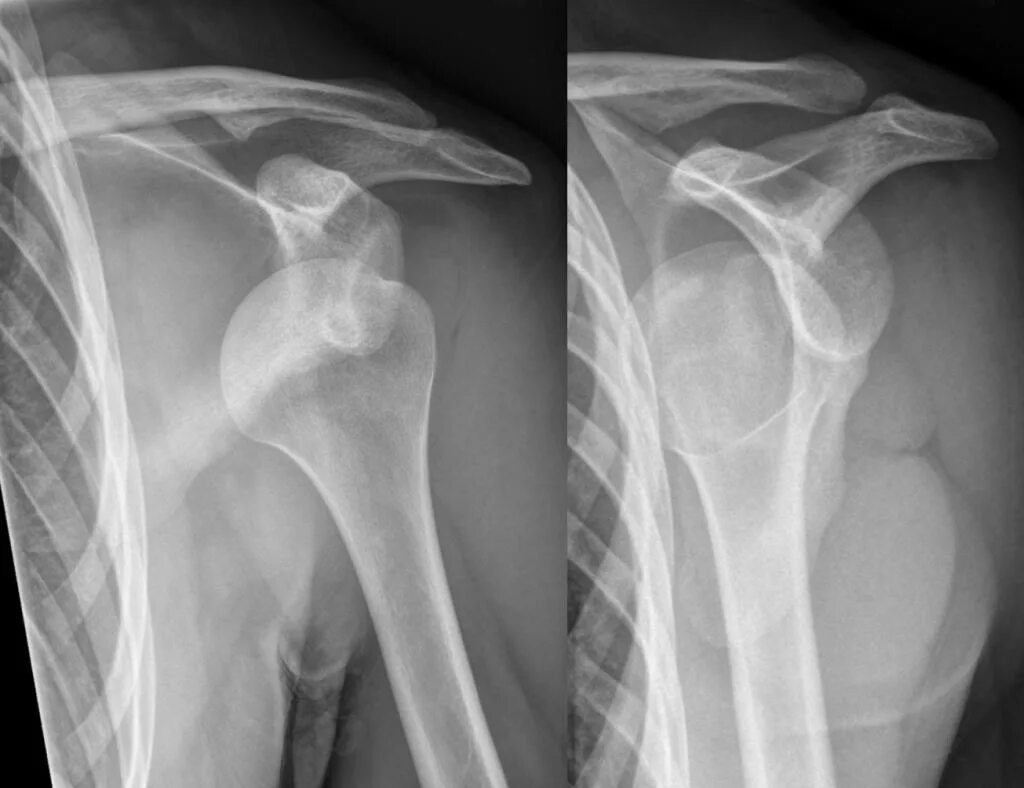

Привычный вывих мкб